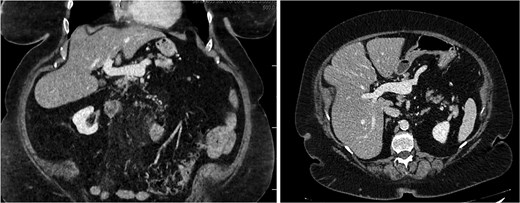

A 76-year-old female with a 3-day history of left upper abdominal pain, vomiting, and haematochezia. Her history included pulmonary embolism, multiple deep vein thromboses, with no ongoing anticoagulation, and an open partial colectomy for complicated diverticulitis a decade earlier. On admission, she was afebrile but tachycardic and showed localized tenderness in the left hypochondrium. Laboratory revealed leucocytosis with a white blood cell count (WBC) of 12 G/L, elevated C-reactive protein (CRP) of 46 mg/L, and hyperlactatemia of 2.6 mmol/l. Enhanced computed tomography (E-CT) revealed jejunal venous ischemia in the left upper quadrant, secondary to extensive porto-mesenteric thrombosis with reduced bowel wall enhancement, distention, and free intraperitoneal fluid (Fig. 1). She was managed conservatively with unfractionated heparin (UFH) with a bolus of 5000 U/l followed by 30 000 U/l/24 h (target INR 0.35–0.7), Piperacillin-Tazobactam, and bowel rest. After 48 h of monitoring in the intensive care unit (ICU), she exhibited marked biological and clinical improvement. E-CT on the third day showed restored bowel wall enhancement and stable porto-mesenteric thrombosis (Fig. 2). She was discharged on therapeutic low molecular weight heparin (LMWH) with enoxaparin sodium 120 mg every 12 h. At the 3-month follow-up, E-CT revealed near-complete thrombus resolution, without intestinal sequelae (Fig. 3).

Abdominal E-CT of the first patient at admission. The white arrows indicate extended porto-mesenteric thrombosis, while the dashed arrows reveal jejunal venous ischemia with a lack of bowel wall enhancement, bowel distension, and free fluid.